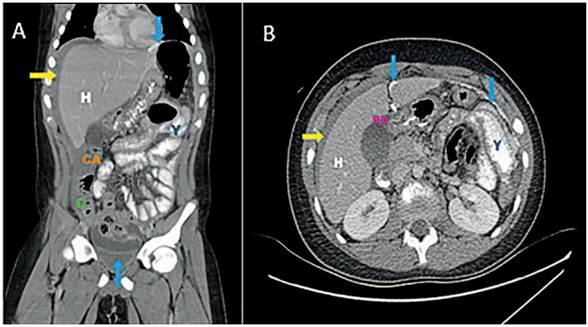

Los laboratorios iniciales informaron leucocitosis de 18.500/mm3, elevación de la proteína C reactiva en 30 mg/L y amilasa sérica en 256 U/L. El ultrasonido evidenció líquido libre en pelvis y en hemiabdomen izquierdo. Se realizó una tomografía computarizada (TC) abdominal con contraste oral y endovenoso que demostró extravasación del medio de contraste, neumoperitoneo y realce del peritoneo (Figura 1).

La úlcera duodenal perforada puede semejar cuadros de apendicitis aguda, como lo reportaron Morrison S y colaboradores en un caso pediátrico, presentación conocida como el síndrome de Valentino 12,18. El neumoperitoneo en la radiografía de tórax en bipedestación tiene una sensibilidad del 75 % para el diagnóstico de UDP 10,17,19. La TC incrementa la sensibilidad diagnóstica al 98 % y permite excluir otros diagnósticos, como la pancreatitis aguda. El uso de contraste oral puede evidenciar la fuga de este a través de la perforación, dando el diagnóstico de certeza 12,20, como se observó en nuestro paciente.